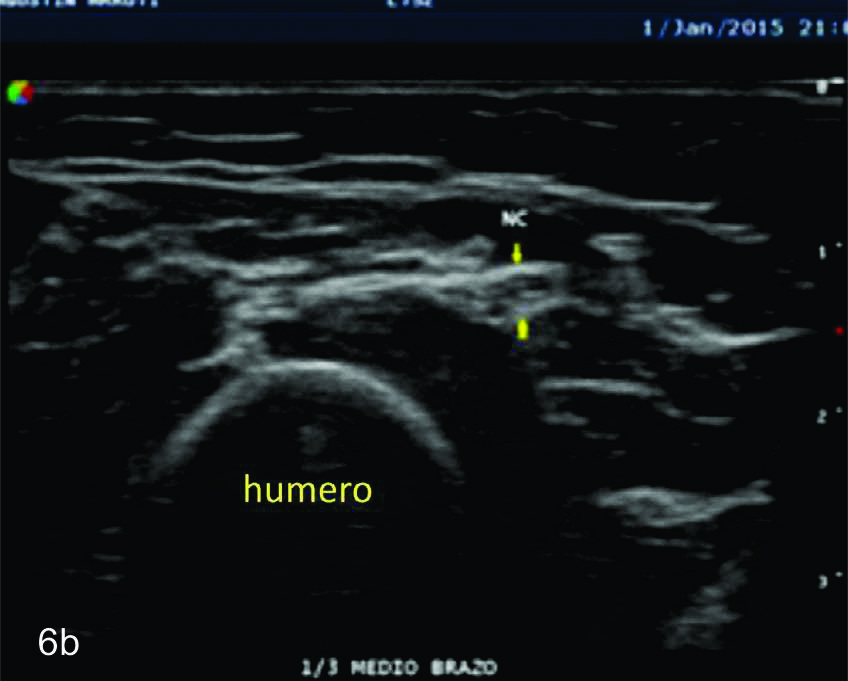

Figura 6

Nervio cubital

B- tercio medio del brazo,

C- tercio distal del brazo,

D- codo en canal epitrocleo-olecraneano,

E- codo- canal cubital,

F- tercio proximal antebrazo,

Figura 7

Serie de cortes axiales del nervio cubital desde su origen a nivel del hueco axilar hasta su terminación a nivel del canal de Guyon. Se identifica el mismo señalado por flechas amarillas y con las letras NC. AH-arteria humeral, PC- músculo prondador cuadrado, P- hueso pisciforme, Línea roja- ligamento anular del carpo, Línea amarilla- túnel de Guyon, Flecha azul- Arteria cubital-. A-tercio distal antebrazo, B- canal de Guyon.